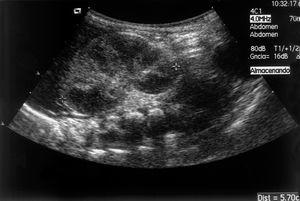

En la analítica destacaba hemoglobina 20,4 g/dl; hematocrito, 63 %; neutrófilos inmaduros/neutrófilos totales, 0,7; creatinina, 96 μmol/l,; AST 159 U/l; creatinfosfocinasa, 3.505 U/l; proteína C reactiva, 25,4 mg/dl. Recibió ampicilina y gentamicina. A las pocas horas presentó hipertensión arterial que necesitó tratamiento farmacológico, con buena respuesta. A las 48 h de vida se detectó una masa en flanco derecho y hematuria isomórfica. La ecografía abdominal mostró un riñón derecho patológico (fig. 1) y el Doppler del riñón derecho era indicativo de TVR (fig. 2). La gammagrafía renal evidenció ausencia de riñón derecho. La tomografía computarizada (TC) abdominal mostró calcificación en la cava infrarrenal (fig. 3). El dímero D fue 4.756 μg/l. La tabla 1 muestra el resultado del estudio biológico de trombosis. Analíticas sucesivas constataron trombopenia (80 x 109/l), incremento de la creatinina (116 μmol/l) y proteinuria (95 mg/h/m2) con normalización posterior. Diuresis conservada. La actividad renina plasmática: 21,5 μg/h/l. No precisó cateterismo umbilical.

Figura 1. Ecografía: corte longitudinal riñón derecho con un aumento global de tamaño, medulares aumentadas de tamaño, disminuidas de ecogenicidad y seno renal disminuido de tamaño.